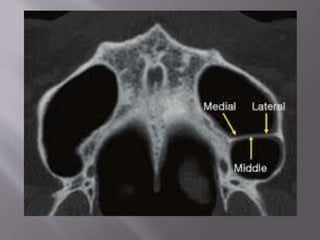

 It is the pneumatic space enclosed inside the

body of maxilla and communicates with the

external environment by way of middle meatus

and nasal vestibule

 It is a pyramidal shape concavity

 It is also known as the Antrum of Highmore, as

it was discovered by an english surgeon

Nathaniel Highmore in the year 1651

 It holds importance to periodontological

consideration

 Height : 36-45mm

 Width : 23-25mm

 Length ( A-P axis) : 38-45mm

 Average vol: 15ml

 Anterior wall : extends from Inferior orbital rim

to maxillary alveolar process

 Superior wall: floor of the orbit

 Posterior wall: separates maxillary sinus and

pterygopalatine fossa

 Medial wall: lateral wall of nasal cavity

 Underwood's septa (or maxillary sinus septa,

singular septum) are fin-shaped projections

of bone that may exist in the maxillary sinus,

first described in 1910 by Arthur S.

Underwood, an anatomist.

 Based on origin they are of 2 types:

1) Primary septa: Formed during maxillary

development and tooth growth

2) Secondary septa: Acquired during

pneumatization of maxillary sinus after tooth

loss

 Location : most of the septa are located

between 2nd premolar and 1st molar region

 Origin : Arises from the medial and lateral wall

of sinus.

 Clinical importnace: septa makes sinus

augmentation processes difficult

 Chances of sinus membrane perforation

depends on the angle between the medial and

lateral wall:

1) > 60 degree angle = 0% chance of perforation

2) 30-60 degree angle has 28.6% chance

3) < 30 degree has 62.5% chance